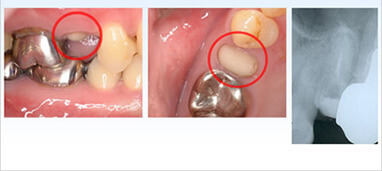

外科的挺出による歯の保存治療

この初診患者様は上顎小臼歯の破折を主訴に来院されました。ご覧のように歯肉の上に歯が全くない状態です。このように歯の根だけが残った場合抜歯もあり得る状態ですが根の長さと厚みが十分あれば保存は可能です。

しかし根が歯肉の中に埋もれた状態では精密な歯型も取れませんし繰り返し揺さぶられる力に抵抗出来ず簡単にかぶせ物は外れ、外れるだけでなく根自体が割れ抜歯に至ってしまいますが意図的に歯を引っ張る(挺出)ことでそれは改善します。歯を引っ張る方法には矯正的、外科的と2つの方法があります。今回はそのうちの外科的挺出をご紹介いたします。

外科的挺出の症例

初診時口腔内、レントゲン写真

歯肉の上に的数ミリ歯根が出るよう慎重に外科的に引っ張り、安定するまで約1ヶ月固定

固定撤去後、かぶせ物の土台の一部をレジンで築造

土台に仮歯を装着し、しばらく経過観察

セラミック冠を被せ治療完了